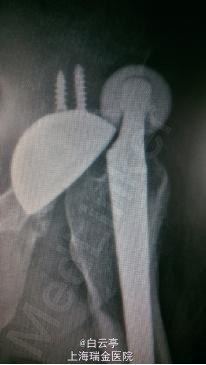

主诉: 左侧髋关节疼痛伴活动受限1天 现病史:患者1天前翘“二郎腿”时忽感左髋疼痛,活动不能。疼痛局限于髋部,不伴腰痛,无下肢放射痛。患者曾于半年前行左侧THA术。

查体: 神清,精神差,生命体征平稳,左侧髋关节外旋畸形,活动受限,疼痛拒按。双下肢血运可。 辅查: X线片示:左侧人工髋关节脱位。

诊断: 左侧髋关节脱位 治疗:左侧髋关节闭合复位术。常规麻醉,将左髋关节外旋,牵拉后内旋,复位后透视下见关节已复位。复位后予以人字形石膏固定1周。